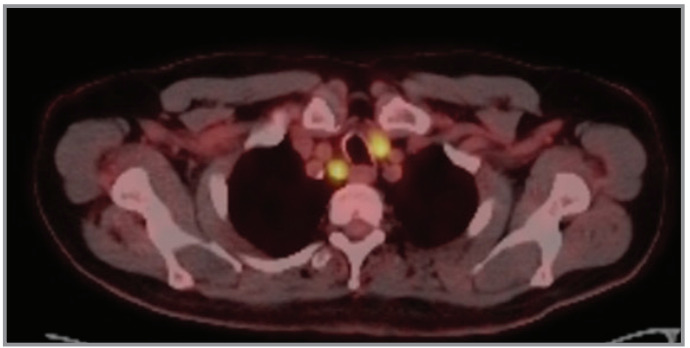

Endobronchial ultrasound-guided transbronchial needle aspiration (EBUSTBNA) is a minimally invasive diagnostic tool used for the evaluation of mediastinal lymphadenopathy. It is a safe procedure, but complications such as bleeding and infection may occur. We report a case of a patient who developed a subcutaneous abscess abscess and mediastinitis after EBUSTBNA. A 75-year-old male with a history of right nephrectomy due to renal cell carcinoma and lung adenocarcinoma history underwent EBUS-TBNA for the evaluation of a right upper paratracheal lymph node. Two weeks after the procedure, the patient presented to the emergency department with skin induration and erythema on the right clavicular area. A non-contrast neck and thorax CT scan was performed, which revealed an extensive subcutaneous abscess on the right clavicular area, extending to the supraclavicular region. The patient was hospitalized, and empirical intravenous antibiotics were initiated due to deep neck infection. Repeated drainage of the subcutaneous abscess was performed. Bacteriologic examination revealed Streptococcus mitis. The patient showed improvement with antibiotic treatment, and a follow-up ultrasound showed a decrease in the size of the abscess and was discharged approximately four weeks after hospitalization. Although very rare, serious infectious complications may develop after EBUSTBNA, and our case report is an important example regarding its management process.